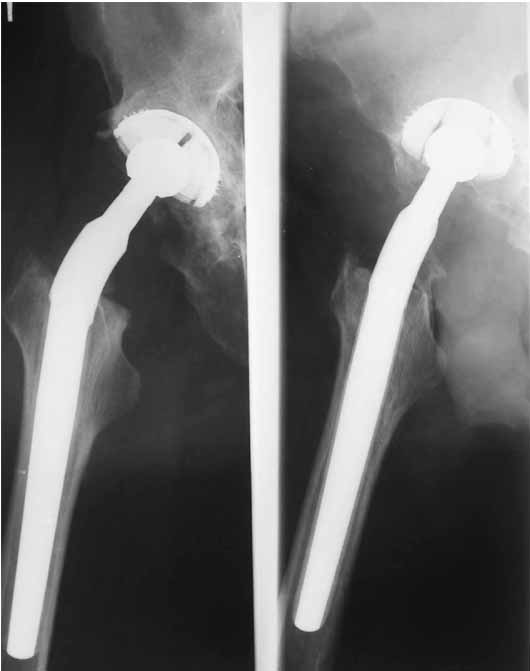

Дорогие коллеги.Мой хороший товарищ, сам травматолог-ортопед, прооперирован 1,5 мес назад. Естественно, начались проблемы. Хотелось бы узнать ваше мнениеи, главное,что делать дальше... Итак:Мужчина 50 лет.Д-з: Посттравматический деф.артроз правого тазобедренного сустава с выраженным болевым синдромом, стойкой комбинированной контрактурой иукорочением 3 см. Анамнез: 10 лет назад - сочетанная травма головы, груди, конечностей, таза... перелом заднего края вертлужной впадины и вывих бедра справа.Лечился консервативно. 25.05.94 - операция тотальное эндопротезирование правого тазобедренного сустава бесцементным эндопротезом (чашка Споторно 52, ножка Вагнера 225/21, головка L), дополнительная фиксация в кокситной гипсовой повязке в течение 3 нед. Спустя месяц после операции при поворачивании на бок в кровати произошел вывих головки эндопротеза. Под наркозом вывих вправили. Вот 10 дней лежит в постели. Что необходимо делать? Рентгенограммы до операции и после. Рентгенограммы в положении вивиха у меня отсутствуют. Ну наверное они и не столь важны, ведь вывих-то вправили. Учреждение и фамилию пациента, нашего коллеги, называть не буду. Он попросил меня собрать мнения - как ему жить дальше. Заранее благодарен. С уважением Александр Артемьев

Если же вывих произошел по причине неправильной ориентации ножки (чего по снимкам нельзя исключить), то конечно же он будет повторяться и

постельный режим тут ничем не поможет. Необходима ревизия с заменой неправильно имплантированного компонента и тщательным восстановлением капсулы и мышц в зоне сустава...

1. Вертикальное положение чашки;

2. Нарушение угла антеверсии ножки (судя по изображению малого вертела

на послеопреационной рентгенограмме).

3. Комбинация этих двух причин.

4. Видимо, тенденция к вывиху была уже на столе - вот Вам и кокситная повязка с надеждой на фиксацию протеза рубцом.

Сан Саныч,

Консультировать вывихи по рентгенограммам, не зная хода операции, дело не очень благодарное. Я думаю, что с датой операции Вы ошиблись и это был 2004 год? Тем не менее. Настораживают два фактора. Первое - не видно большого вертела. Если с мышцами обошлись грубо и их отсекли, то это очень грустно и нужна "связанная" пара, т.н. "constrain cup". Смущает хорошо прослеживаемый малый вертел и небольшая ретроверсия чашки. Возможно это (избыточная ретроверсия ножки и чашки) могло послужить причиной вывиха. Обычно гипсовая повязка после операции не накладывается, значит, были глубокие сомнения у оперировавшего хирурга. В этом случае - ревизия с перестановкой как минимум - ножки, а как максимум - обоих компонентов.